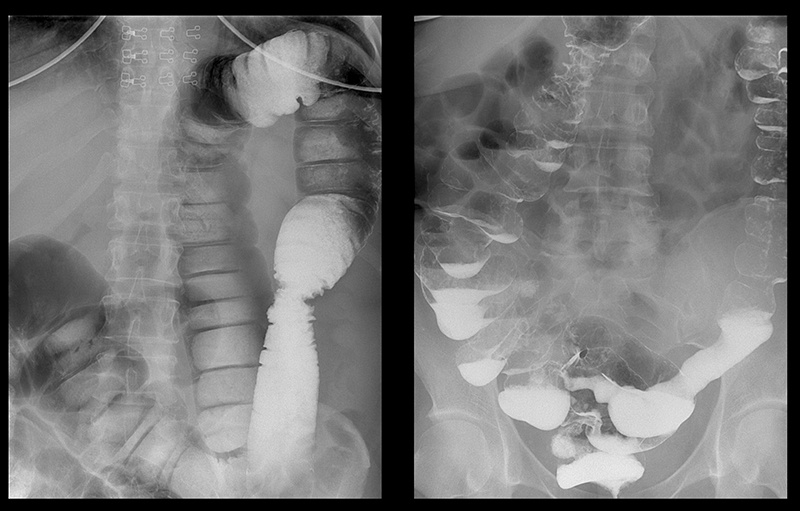

Наприклад, хронічний гастрит або виразкова хвороба можуть призвести до появи запальних змін в шлунковій стінці, що можуть бути передраковими утвореннями. Неусунення запорів або діареї може призвести до пошкодження слизової оболонки кишечника та збільшити ризик розвитку раку кишечника.

Більшість симптомів раку кишечника проявляються досить явно, і їх важко не помітити. У пацієнтів із цим захворюванням на початковій стадії часто з'являються:

- закрепи;

- сильне газоутворення та метеоризм ;

- печія;

- кислотний рефлюкс;

- проблеми із ковтанням;

- нудота блювота;

- діарея та часті симптоми розладу шлунка.